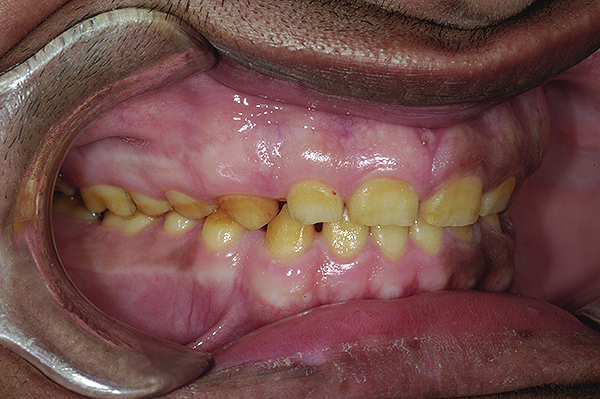

Figure 3. Preoperative 1:2 retracted right lateral view.

Figure 3

Figure 4. Preoperative 1:2 retracted left lateral view.

Figure 4

The authors report on a 21-year-old patient who presented with severe discoloration and mild sensitivity of teeth (Figure 1). The teeth visible in his smile were very short, unsightly, and unbecoming for his age.

A thorough clinical examination and analysis were carried out to assess the esthetic and functional problems of the patient (Figure 2 through Figure 7). The medical history was non-contributory, except for mild leukoderma. Temporomandibular joint (TMJ) function was within normal range.